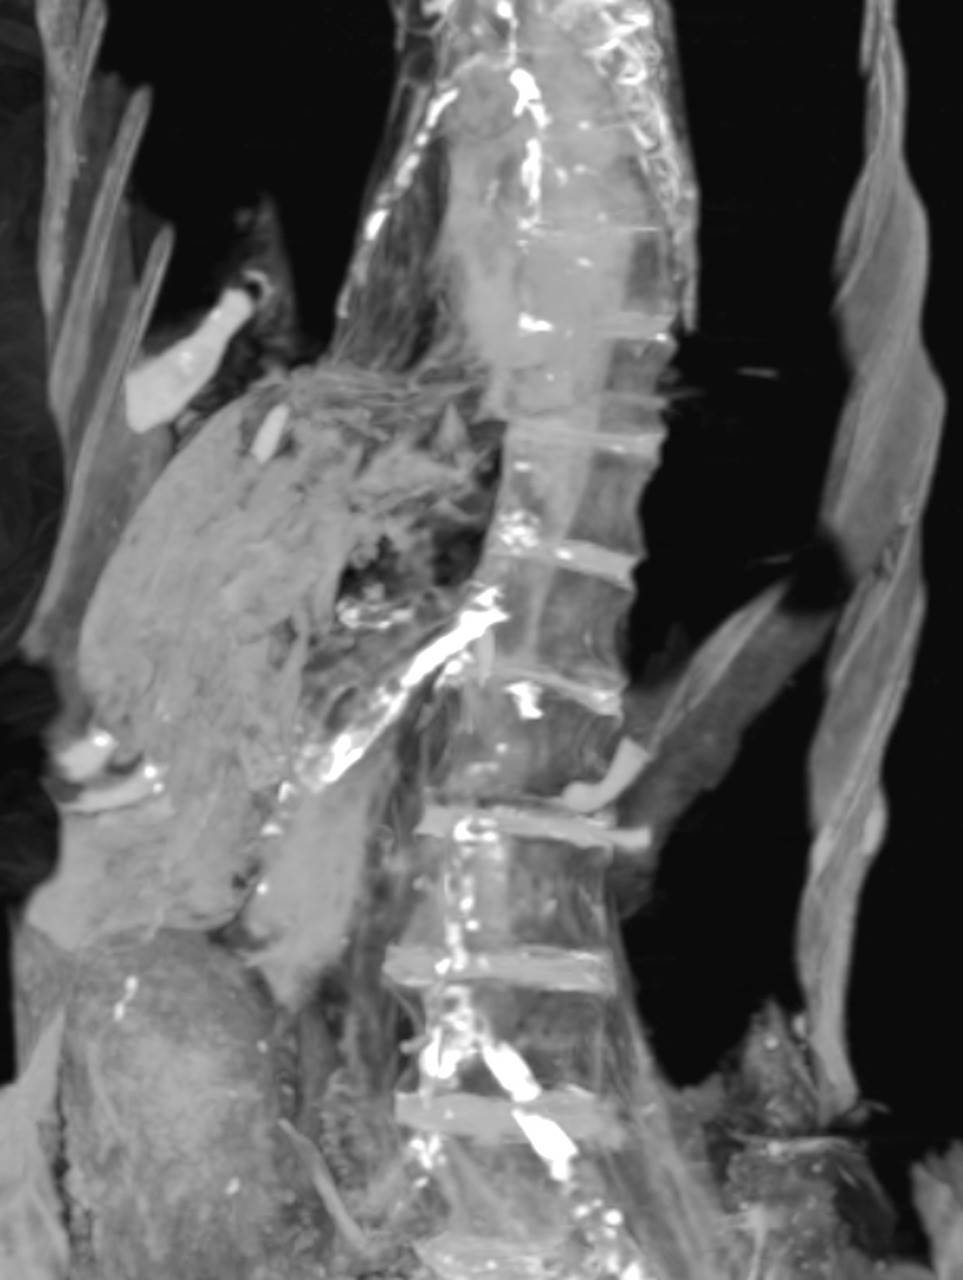

فأثبت فحص الأشعة المقطعية ل ”مومياء المرأة غير المعروفه إىه” انها عانت من تصلب في شرايين القلب التاجية الأيمن و الأيسر و كذلك شرايين الرقبة و شريان الأبهر البطني والحرقفي، وكذلك شرايين الطرفيين السفليين و الساقين.

وأثبتت العديد من الدراسات السريرية في الوقت الحاضر أن مرض تصلب الشريان التاجي للقلب يعد السبب الرئيسي للوفاة المفاجئة لدى البالغين .و يوصي الطب الحديث في مثل هذه الحالة الطبية الخطيرة المماثلة لحالة مومياء المرأة الصارخة إلى اعطاء الأدوية التي تذيب جلطات الأوعية الدموية و ربما قسطرة قلبية و ذلك لمنع أو الحد من تلف عضلة القلب .وتفترض الدراسة التي اجراها دكتور زاهي حواس و دكتورة سحر سليم أن جلطة الأوعية التاجية ل”مومياء المرأة غير المعروفه إىه”" سببت تلف عضلة القلب مما أدى إلى موتها الفجائي.

و تفترض هذه الدراسة ان الأميرة ماتت فجأة بنوبة قلبية و هي على وضع الجسد الحالي ساقاها مثنية و ملتفة عند الكاحل. و تسبب الموت في ميل الرأس إلى الجانب الأيمن و ارتخاء عضلات الفك مما أدى الى فتح الفم. و تشير الدلائل أن المتوفاه ظلت لفترة كافية لعدة ساعات على هذه الوضعية قبل ان يتم اكتشاف الجثمان فأدى التشنج الذي يعقب الموت الى تيبس العضلات و المفاصل و أبقاء مومياء الأميرة على وضعية الوفاة هذه فلم يتمكن المحنطون من تأمين أغلاق الفم أو وضع الجسد في حالة الاستلقاء كما كان المعتاد مع باقي المومياوات. فيبدو انه لم يهمل المحنطون عملهم عن عمد و لكن ظروف الوفاة أدت لوضعية المومياء هذه و الغير معتادة. وأظهرت صور فحص الأشعة المقطعية ان المحنطون لم يستخرجوا مخ المومياء حيث لا يزال يرى المخ بداخل تجويف الجمجمة و لكنه يميل الى الجانب الأيمن و ذلك لوضعية الجسد على هذا الجانب عند الموت و بعد التحنيط.